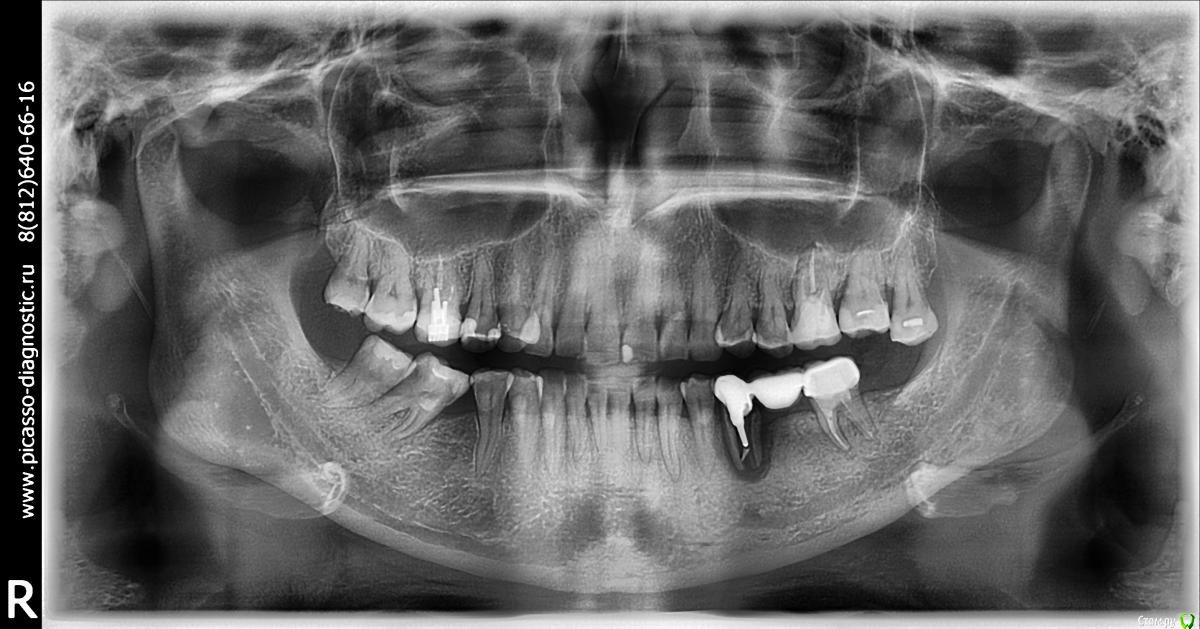

alboard Опубликовано 19 апреля, 2017 Поделиться Опубликовано 19 апреля, 2017 35 уже удален, вестибулярно кортикальная отсутствует. Планируется работа из разряда бюджетных. Соответственно вопрос: насколько будет актуальна конструкция на имплантате в области 36 с консолью в области 35го? 1 Ссылка на комментарий

TIGER Опубликовано 19 апреля, 2017 Поделиться Опубликовано 19 апреля, 2017 что с костью с дистальной 34?это тоже возьмите в о внимание Ссылка на комментарий

руслан64 Опубликовано 20 апреля, 2017 Поделиться Опубликовано 20 апреля, 2017 37 ослаблен и раскачен. Может подумать о 36+37 с консолью на 35? Ссылка на комментарий

Dman Опубликовано 12 мая, 2017 Поделиться Опубликовано 12 мая, 2017 (изменено) Что если просто снять мост, удалить 35, перелечить 37. через 3-4 месяца котрольное кт и установка 35,36+коронка на зубе 37. Долго, но надежно и гарантировано оп, 35 уже удален, значит просто контрольное кт и возможно установка с пластикой. Если совсем бюджет, то лучше мост на зубах Изменено 12 мая, 2017 пользователем Dman Ссылка на комментарий